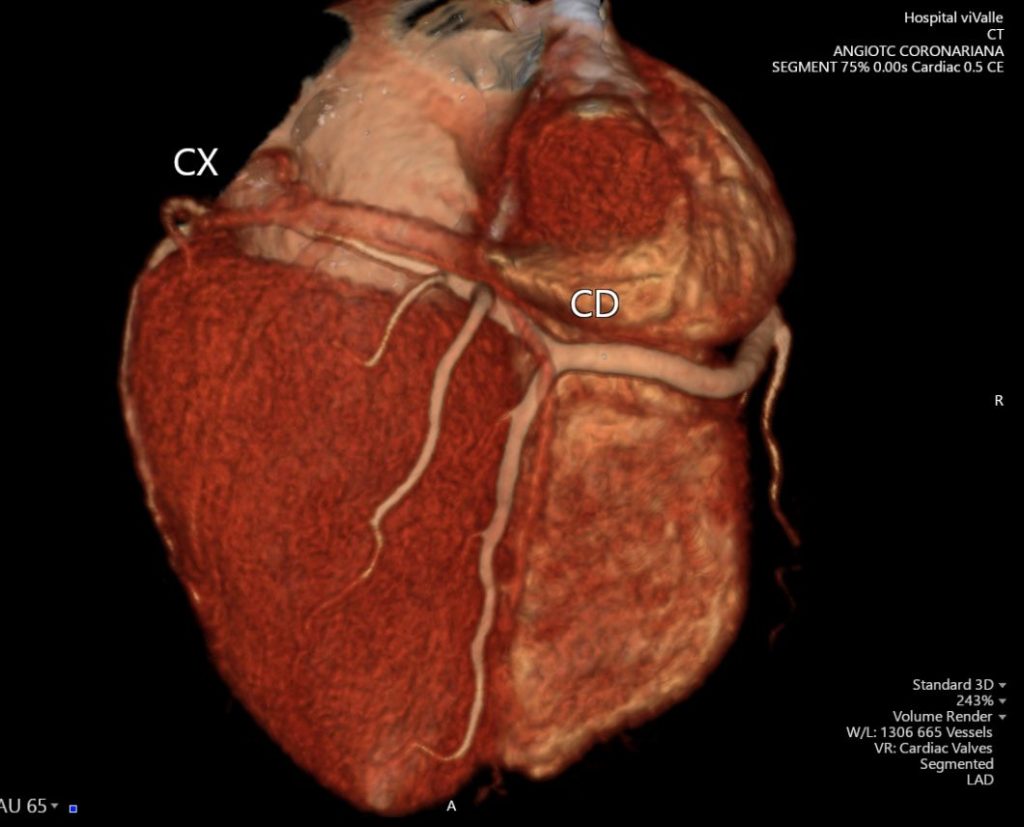

A angioTC de coronárias (CCTA) vem ganhando protagonismo na prevenção primária porque vai além do escore de cálcio: ela identifica placas não calcificadas, muitas vezes invisíveis ao CAC, e que podem representar aterosclerose ativa e risco real mesmo em pessoas classificadas como “baixo risco” pelos escores tradicionais.

Um grande estudo populacional recente (JAMA), com quase 25 mil indivíduos de 50 a 64 anos sem doença cardiovascular conhecida e seguimento de aproximadamente 8 anos, mostrou que a presença de placa não calcificada na CCTA se associou a maior risco de primeiro evento coronário e que a inclusão dessas informações anatômicas melhorou a predição de risco e a reclassificação, principalmente entre os pacientes inicialmente rotulados como baixo risco.

Na prática, isso muda o jogo: detectar precocemente placas não calcificadas permite “antecipar” o diagnóstico da doença coronária, individualizar a prevenção e orientar medidas mais assertivas — especialmente em pacientes que, pelo cálcio ou pelo risco clínico, poderiam ser falsamente tranquilizados.